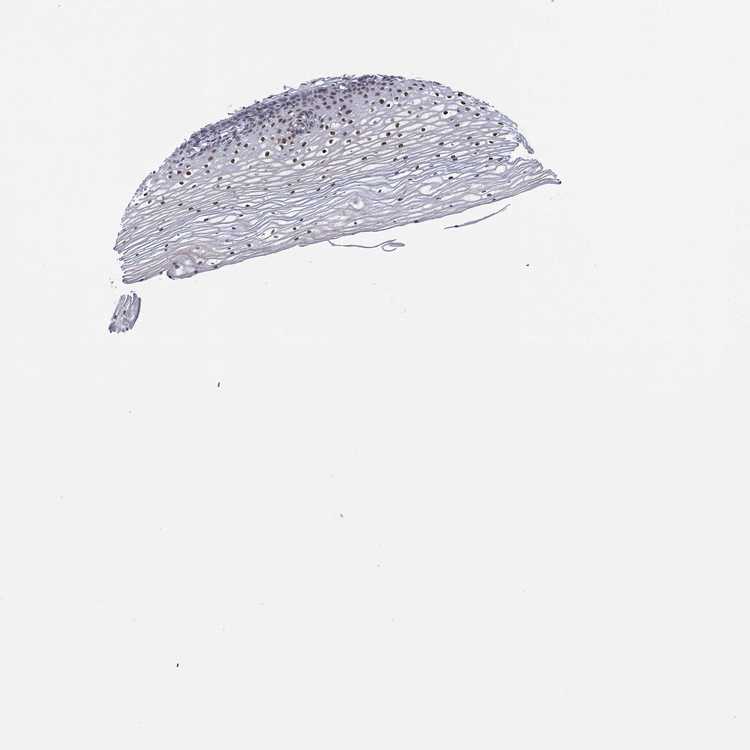

CERVIX - Antibody stainingi

Antibody staining in the annotated cell types in the current human tissue is reported as not detected, low, medium, or high, based on conventional immunohistochemistry profiling in selected tissues. This score is based on the combination of the staining intensity and fraction of stained cells.

Each image is clickable and will lead to virtual microscopy that enables deeper exploration of all samples and also displays staining intensity scores, fraction scores and subcellular localization as well as patient and tissue information for each sample.

Antibody HPA042090

Squamous epithelial cells Medium